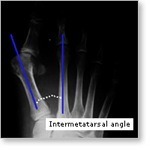

X-rays will be taken to determine the extent of displacement of the bones making up the bunion. The angles shown here help us decide which bunion operation would be the best. This is the angle between the 1st and 2nd metatarsal.

Other surgery performed at Fitter Feet to correct Hallux valgus, include Austin Ostetomies, Lapidus Fusion and opening and closing base wedge ostetomies. The selection of procedure depends on how large the bunion is, and how high the angle is between the 1st and 2nd Metatarsals.